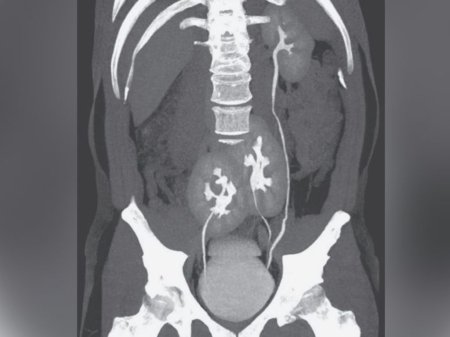

人間には通常2つの腎臓がありますが、この男性は正常な見た目の腎臓が1つと、骨盤の近くで2つが融合していたと言います。

「彼の腎臓の機能は……まったく正常であった。 痛みの原因がすでに診断されていたことと、その他の検査項目に変化がなかったことから、腹部超音波検査と断層撮影によるさらなる検査で十分と判断しました」とForestoは付け加えました。

Having three kidneys is extremely rare, LiveScience says, with fewer than 100 cases reported in literature, according to the Internet Journal of Radiology.